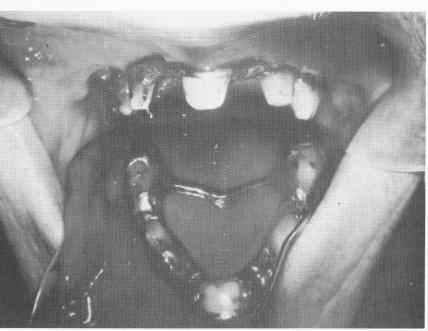

Fig. 10-229. The completed palateless denture with internal clip bars which secured it to the connection bar of the mesostructure. (From Linkow, L. I.: Maxillary endosseous implants, Dent. Concepts 10 [1] :14-24, 1966.)